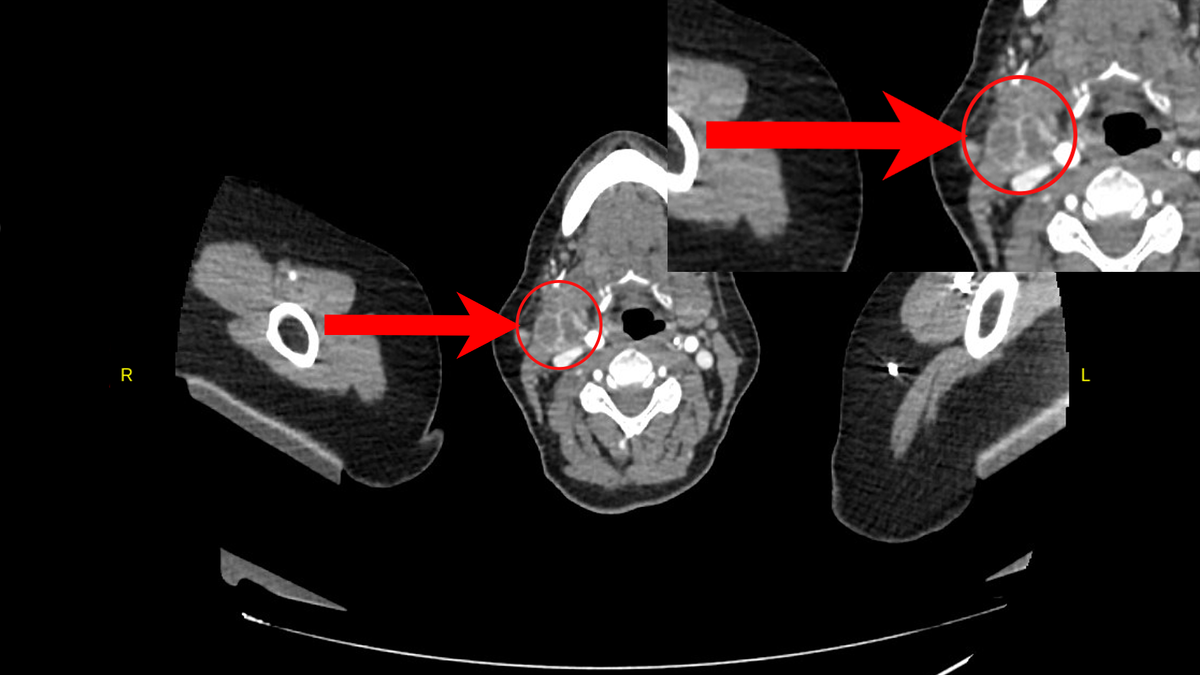

Конгломерат увеличенных подчелюстных лимфоузлов на КТ.

...в подчелюстном пространстве справа определяются узловые структуры с периферическим контрастированием, в центральных отделах пониженной плотности - до 25х20 и 20х21мм...

Увеличенные лимфоузлы на КТ в другой проекции.